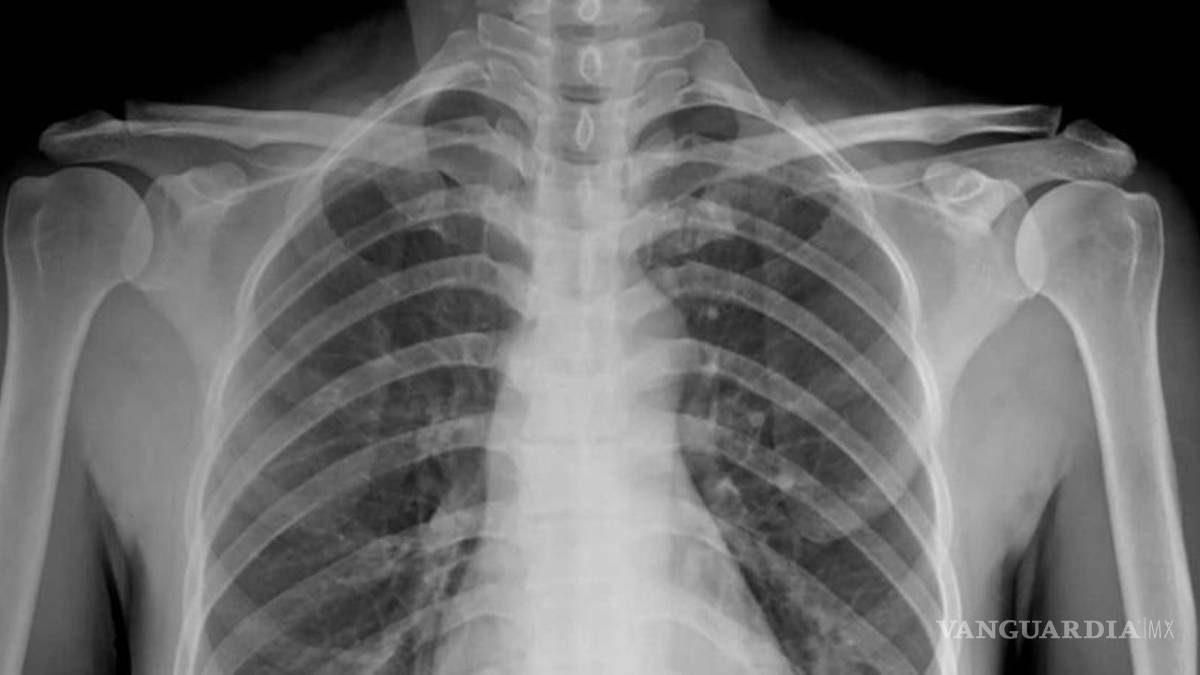

Los pulmones de un paciente sano deberían verse limpios y con mucho espacio negro, que es básicamente aire, mientras un pulmón de un fumador tiene líneas blancas, como una especie de neblina, que son indicativas de cicatrización y congestión.

Sin embargo, los pacientes post covid, muestran pulmones que parecen estar casi completamente blancos, en otras palabras, severamente dañados.